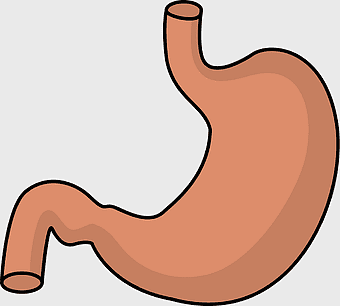

stomach illustration, full stomach anatomy, abdominal organ depiction, human digestive system, gastroenterology graphics, medical illustration artwork, digestive health visual -

human gastrointestinal tract anatomy, human digestive system illustration, gastrointestinal disease symptoms, human body organ diagram, internal organ visualization, medical anatomy study, digestive health awareness -